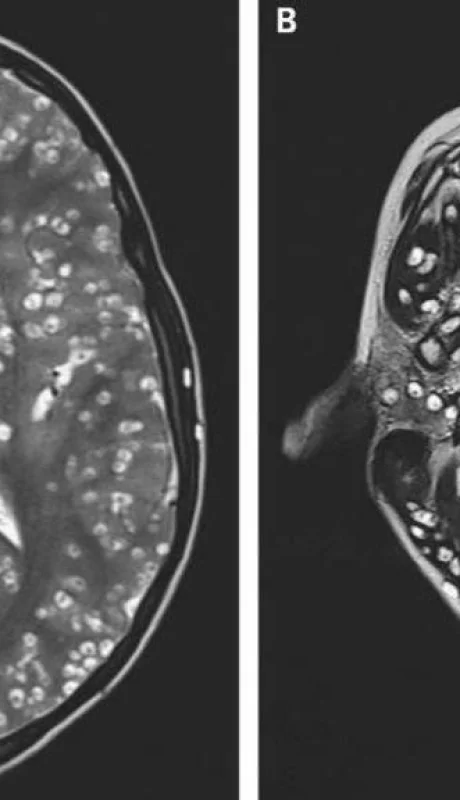

Cisticercosis: murió un joven que tenía huevos en el cerebro